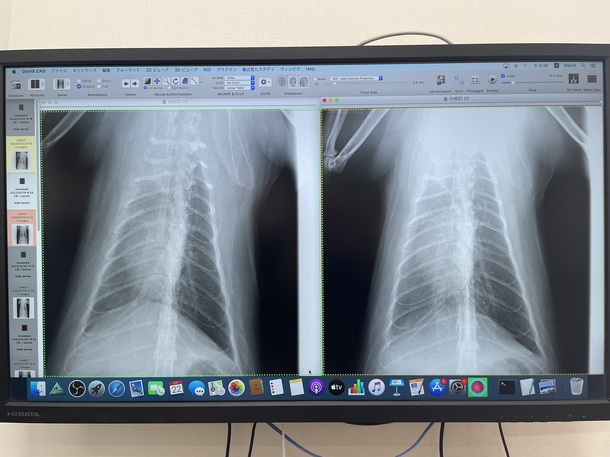

三月の検診に行きました!

膿胸のモヤはそのまま現状維持ですが、ほーんのり薄くなっている様です。心配していた再発は今のところありません!

今日はレントゲン2枚とワクチンとノミの薬2回分で16280円でした。